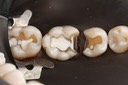

Chris Woo #12 pre-op

Chris Woo #12 caries removal